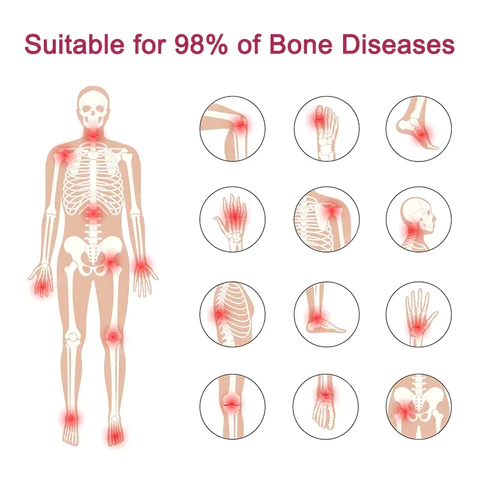

Using BBOJI™ Tigers Oil Spray can treat 98% of arthritis cases.

Include osteoarthritis, rheumatoid arthritis, bursitis, tendonitis, osteoporosis, gout, bunions deformities, ligament sprains and strains, and tennis elbow, etc.

- Suitable for hands, legs, knees, back, hips, feet, knuckles, and other affected body parts